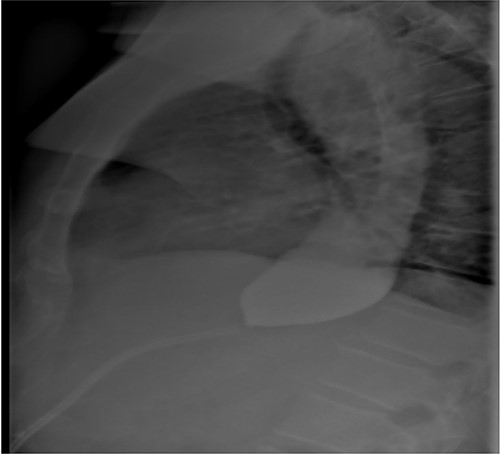

Three months after band removal, the patient reported complete resolution of his symptoms. Repeat gastroscopy demonstrated oesophageal mucosal healing and no residual hiatal hernia. TTE showed that left atrium was moderately enlarged (but to a lesser extent compared to previous study) and normal left and right ventricular systolic function and dimensions with estimated left ventricular ejection fraction of 60%. Furthermore, the post-operative Barium swallow study (Fig. 4) demonstrated a 6.7-cm oesophageal dilatation and dysmotility. There was no significant delay in passage of barium into a non-distended stomach. Since band removal his weight had increased by 17 kg (112.8 kg, BMI: 36.4). Further discussions with the patient led to laparoscopic sleeve gastrectomy a month later (Fig. 5).

Post-gastric sleeve barium contrast swallow study demonstrating ongoing oesophageal dilatation, but passage of contrast into remnant stomach.